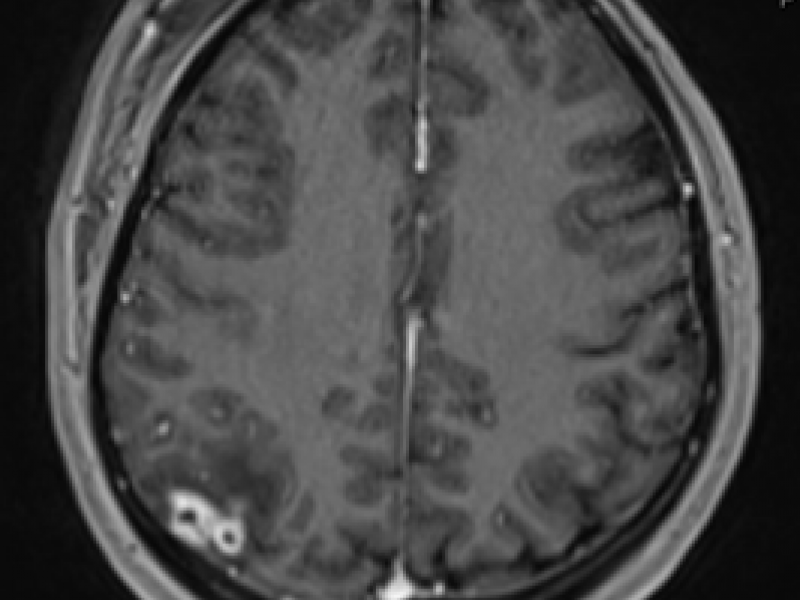

Imaging Case Answer: Neurocysticercosis

August 25 2016

The diagnosis of Neurocysticercosis was made by the